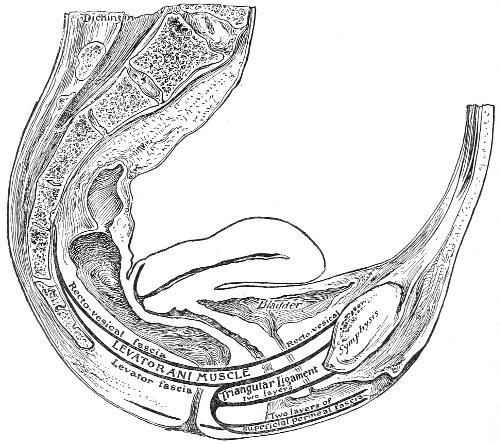

An accurate knowledge of the anatomy and mechanism of the female perineum is essential to an understanding of the nature and treatment of injuries to this structure. The anatomical structures lying between the anus behind and the symphysis pubis in front are those that most directly interest the gynecologist. Proceeding from 57 below upward, we find the following structures lying in superimposed planes: the skin, the superficial fascia, the deep layer of the superficial fascia, the transversus perinæi and the sphincter vaginæ muscles, the anterior layer of the triangular ligament, the posterior layer of the triangular ligament, the levator ani muscle (Fig. 19).

Fig. 20.—Dissection of female perineum, showing the deeper structures after removal of the levator and sphincter ani muscles.

Fig. 21.—Muscular floor of the pelvis seen from above.

Fig. 22.—Sagittal section showing relations of the several layers of fascia within the pelvic floor (Dickinson).

The vagina extends, as a transverse slit in the pelvic floor, upward and backward, approximately in the direction 60 of a line drawn from the ostium vaginæ to the fifth sacral vertebra. It is approximately parallel with the conjugate of the brim, so that when the woman is erect the long axis of the vagina is inclined at an angle of 60° to the horizon. The vagina is not a vertical open tube: it is a slit in the pelvic floor, in health always closed by the accurate apposition of the anterior and posterior walls (Fig. 21). The anterior vaginal wall is about 2½ inches long in a vertical mesial line. The posterior vaginal wall is about 3½ inches long. The vaginal walls are triangular in shape, being broader above than below. The shape of the normal vagina at the pelvic outlet is shown by Fig. 23. The section here shows the vaginal 61 slit of the shape of the letter H. The portions of the slit extending backward and somewhat outward are called the vaginal sulci or furrows. They are directions of diminished resistance in which tears are liable to occur.

Fig. 23.—Section illustrating the characteristic form of the vaginal cleft (Henle): Ua, urethra; Va, vagina; L, levator ani; R, rectum.] 62